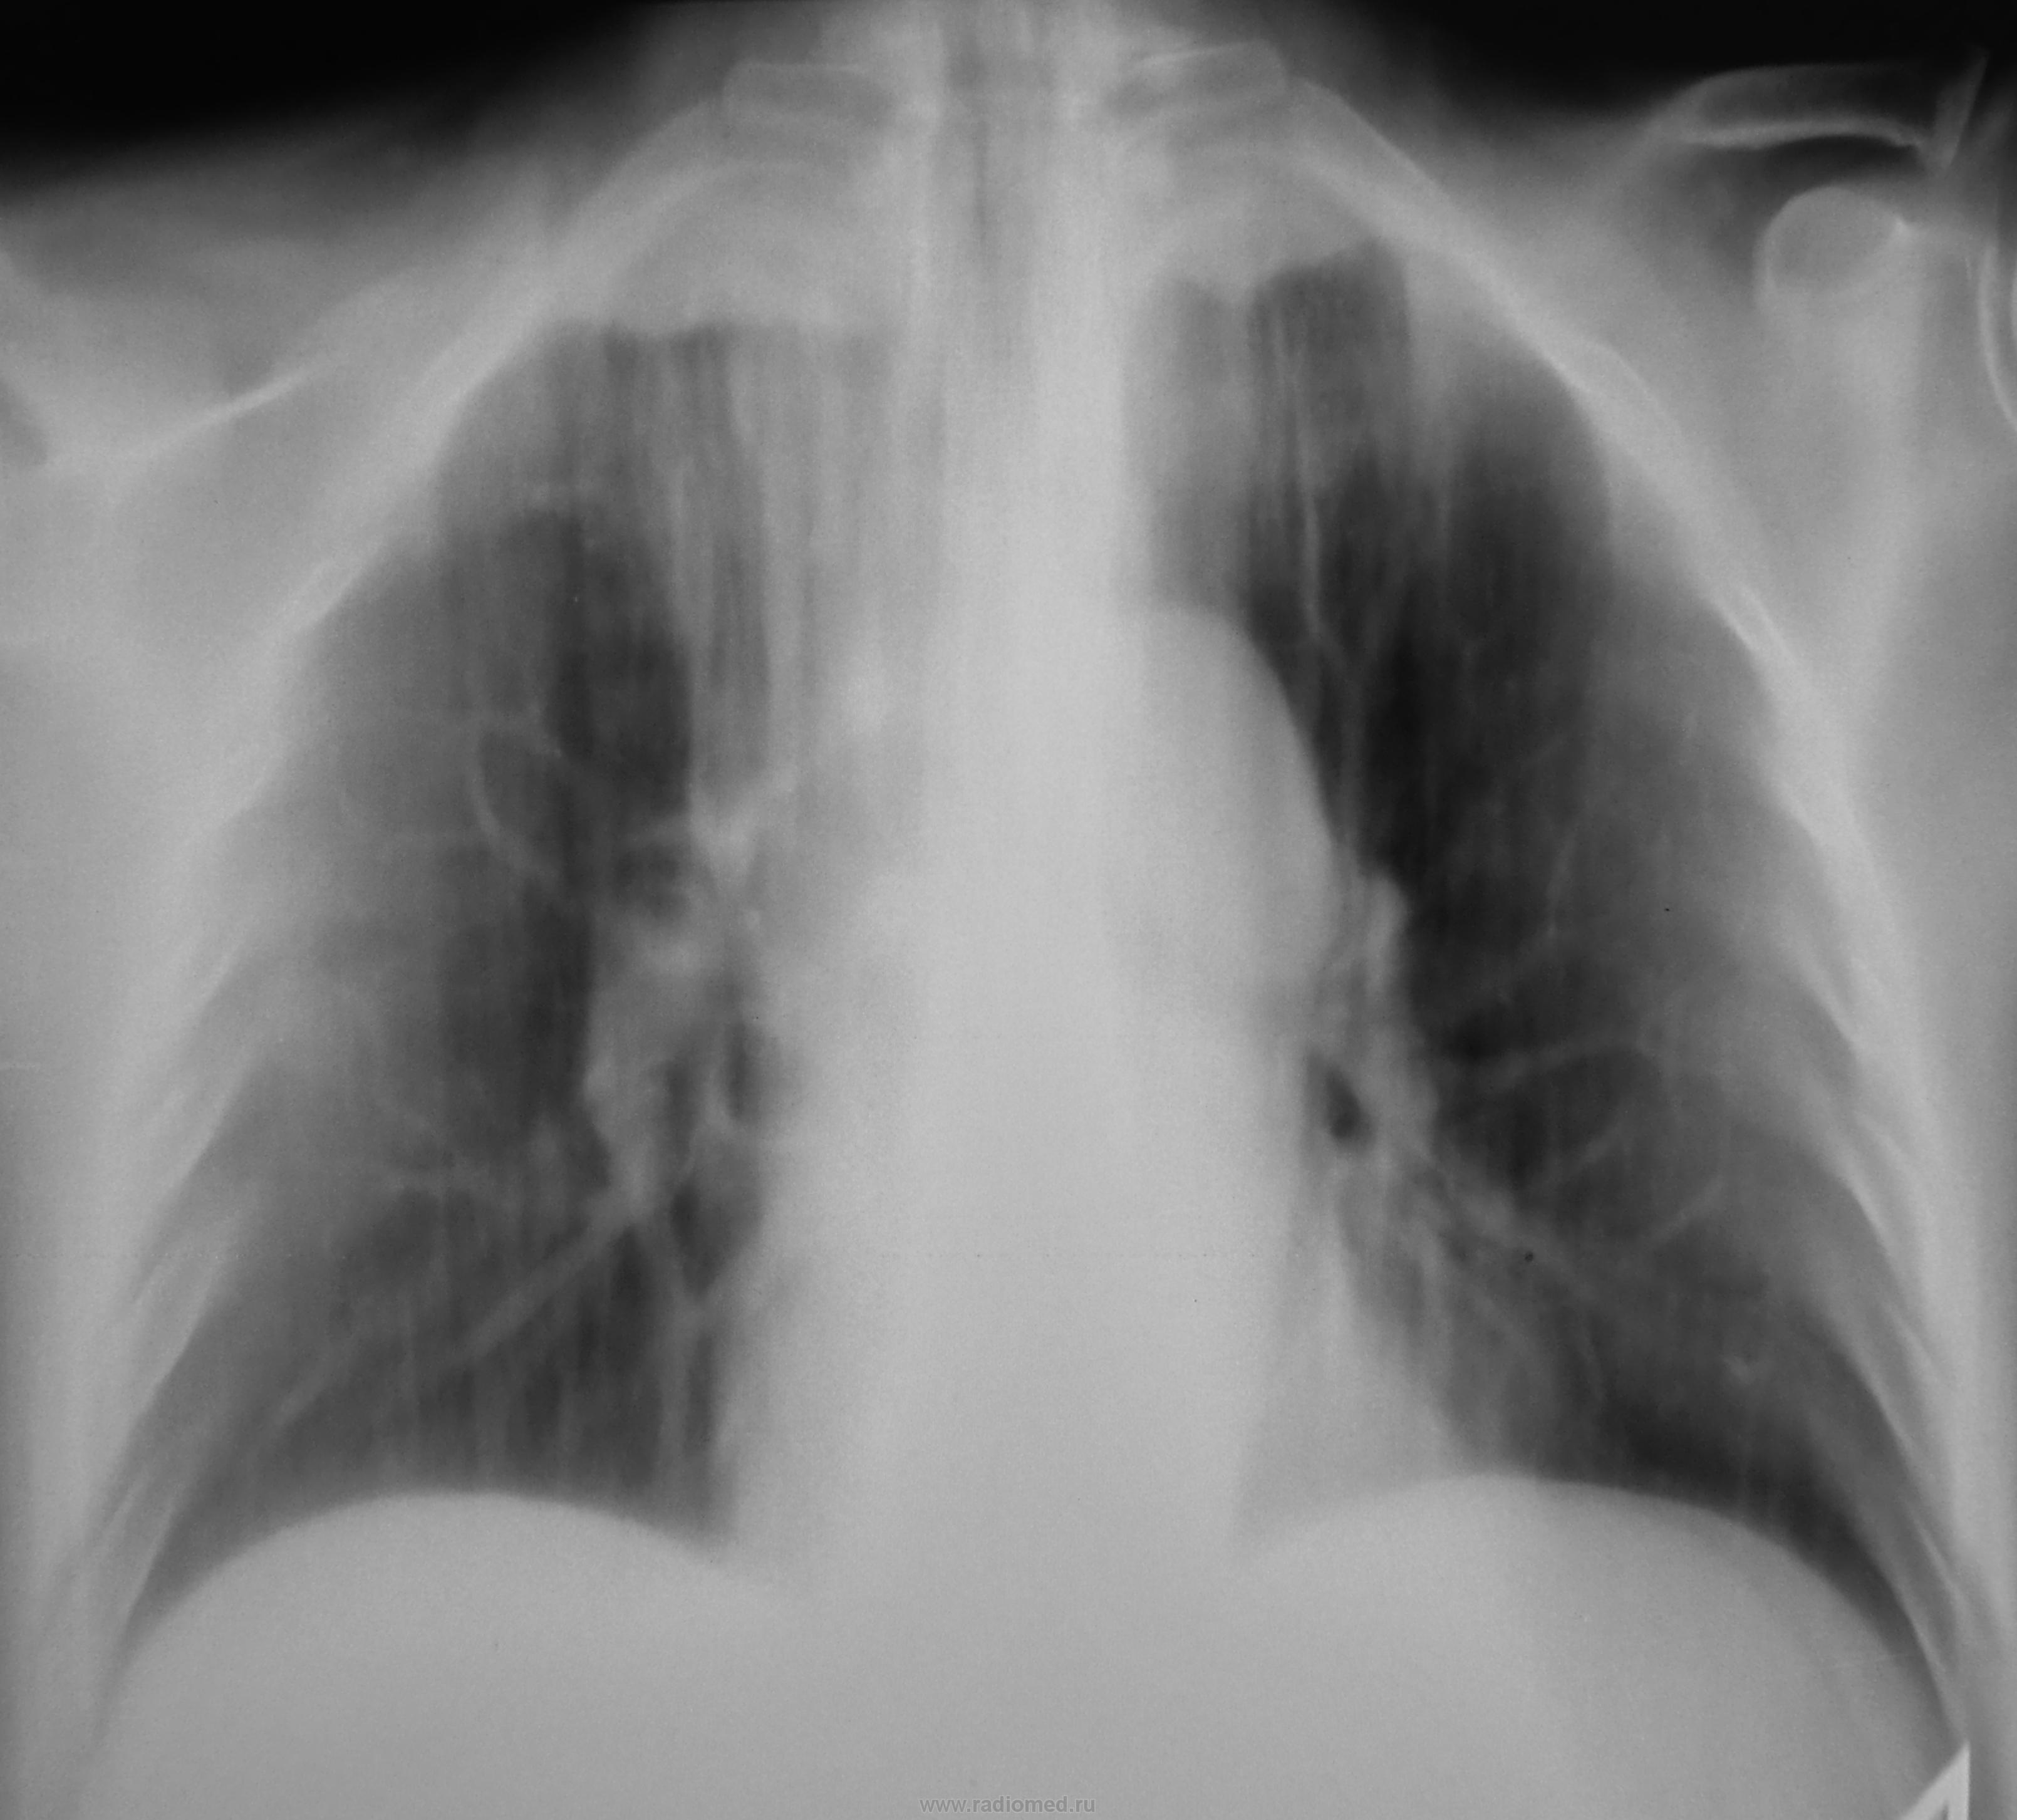

Пол пациента: Мужской пол Тип патологии: Другое Область исследования: Грудная клетка и верхние дыхательные пути Методы исследования: Rg Ранее болел туберкулёзом. Сегодня был направлен терапевтом с диагнозом пневмонии https://radiomed.ru/sites/default/files/styles/case_slider_image/public/user/12/2.dscn1413.jpg?itok=ddIwdutI https://radiomed.ru/sites/default/files/styles/case_slider_image/public/user/12/3.dscn1414.jpg?itok=BaDHOskS https://radiomed.ru/sites/default/files/styles/case_slider_image/public/user/12/4.dscn1415.jpg?itok=72LWEAHd ID:27835 Чт, 11/04/2013 - 09:53 #1 НБ Не на сайте Был на сайте: 11 лет 5 месяцев назад Зарегистрирован: 07.11.2012 - 19:55 Публикации: 84 утолщена апикальная плевра. Справа в верхней доле фиброз?. Но на ТГ не виден ВДБ, нет ли ателектаза в/доли. Н.Б. Чт, 11/04/2013 - 16:16 #2 brainmodel Не на сайте Был на сайте: 2 месяцев 2 недели назад Зарегистрирован: 18.03.2010 - 22:04 Публикации: 2881 Архив. Затем все разговоры. Verum plus uno esse non potest. Чт, 11/04/2013 - 19:26 #3 maker4ik Не на сайте Был на сайте: 8 лет 7 месяцев назад Зарегистрирован: 19.10.2011 - 17:49 Публикации: 2682 Не увидела пневмонию. И свежих очагов тоже. Чт, 11/04/2013 - 19:55 #4 Сергей Кузьминов Не на сайте Был на сайте: 1 год 2 недели назад Зарегистрирован: 06.10.2012 - 15:51 Публикации: 11813 Активного лёгочного процесса нет.Посттуберкулёзные изменения есть.

утолщена апикальная плевра. Справа в верхней доле фиброз?. Но на ТГ не виден ВДБ, нет ли ателектаза в/доли.

Не увидела пневмонию. И свежих очагов тоже.

Активного лёгочного процесса нет.Посттуберкулёзные изменения есть.